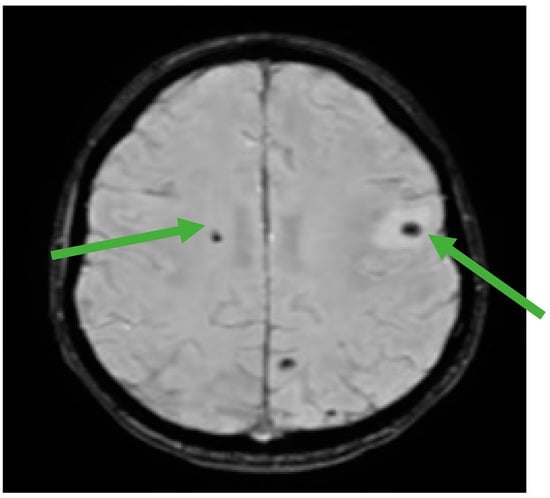

Figure 5.

Brain MRI showing multiple hemorrhagic metastases at the supratentorial and cerebellar level (green arrows).

In the meantime, we monitored beta HCG and there were slightly increased values, but when the beta HCG was at 126,224 mIU/mL, we established the progression of the disease. Although it was not a standard treatment and there was a low chance to have a responsive disease in the fourth line setting, the fact that it was a young patient with a good performance status influenced our decision to start salvage chemotherapy with cisplatin–epirubicin regimen for four cycles (epirubicin 90 mg/sqm day 1, cisplatin 20 mg/sqm day1–5 qw3). After the fourth cycle, the patient started to have recurrent seizures and a new brain MRI showed multiple hemorrhagic supratentorial and cerebellar metastasis on both sides of the brain. Palliative whole brain radiotherapy was immediately initiated, improving the patient’s condition I, Figure 5. Unfortunately, the patient seems to continue to progress with an increased beta HCG of 90,319 mIU/mL (Figure 6).